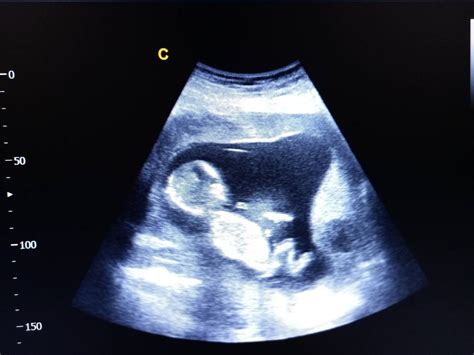

Când vine vorba despre sarcină, săptămâna 6 este marcată de obicei de ecografia de confirmare a sarcinii, când vei putea probabil să auzi pentru prima oară inima viitorului tău copil. Embrionul are un aspect curbat și pare să prezinte o coadă în miniatură.

În săptămâna 10 de sarcină pavilioanele urechilor și structura internă a acestora încep deja să se formeze. Chipul bebelușului îți permite să distingi buza superioară și două nări minuscule. Maxilarul și mandibula cresc și conțin, deja, viitorii dinți de lapte. Inima este complet formată și bate cu o frecvență de 180 bătăi pe minut. Bebelușul începe să facă mișcări bruște, ca niște zvâcniri, vizibile ecografic.

E momentul să mai faci o ecografie acum, mai ales dacă nu ai nici una, și poți să-ți iei și partenerul cu tine. Sarcina este o chestiune de cuplu, nu-i așa?

Nu se poate descrie în cuvinte sentimentul de a-ți vedea prima dată pe ecran bebelușul!

O ecografie te asigură că bebelușul este cu „capul în jos” și că se poate naște natural.